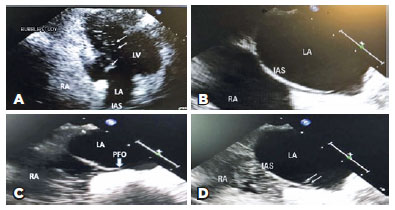

A 43-year-old male with a history of hypertension presented with sudden painless right vision loss. Examination revealed best-corrected visual acuities of no light perception (right) and 20/25 (left) and right relative afferent pupillary defect. Intraocular pressures were normal, extraocular movements were full, and anterior segments were unremarkable. Dilated fundus examination revealed a right pale, moderately swollen optic nerve, macular pallor with a cherry red spot, and box-carring blood flow in several vessels. However, emboli were not detected. The left eye was normal. Right central retinal artery occlusion was diagnosed, and the patient was transferred to the Stroke Unit for admission and management. Blood pressure on admission was 136/92 mmHg. Examination the next day revealed resolution of box-carring and a more distinct cherry red spot (Figure 1A). The left eye remained normal (Figure 1B). Fundus fluorescein angiogram (FFA) revealed no abnormalities and no evidence of emboli, arterial narrowing, staining, or areas of non-perfusion. Laboratory workup revealed elevated total cholesterol of 220 mg/dL (normal= 120-200mg/dL): high density lipoprotein of 33 mg/dL (normal = 27-67 mg/dL), low density lipoprotein of 154.6 mg/dL (normal = 100-129 mg/dL), and triglycerides of 162 mg/dL (normal = 40-160 mg/dL). Complete blood count, including platelet count, erythrocyte sedimentation rate (ESR), C-reactive protein (CRP), coagulation profile (PT/PTT), glycosylated hemoglobin (HbA1c), urine toxicology, anti-cardiolipin, lupus anticoagulant, antinuclear antibodies (ANA), antineutrophil cytoplasmic antibodies (ANCA), homocysteine levels, angiotensin converting antibody (ACE), syphilis antibodies, and C and S proteins were normal. Head and neck magnetic resonance imaging and magnetic resonance angiography (MRI/MRA) were normal, and carotid duplex was negative for stenosis or occlusions. Holter monitor did not reveal any arrhythmia and venograms failed to disclose venous thrombosis. TTE (S5 transducer, Philips iE33 model, Koninklijke Philips N.V., Amsterdam, Netherlands) was initially normal; however, a subsequent bubble study revealed an interatrial right to left shunt (Figure 2A). TEE (X5 transducer, Philips iE33 model) performed to further define the shunt revealed a small interatrial tunnel, characteristic of PFO (Figures 2B-D).

Our case demonstrated a young patient presenting with CRAO with initially negative cardiovascular and neurologic workup. Although initial TTE bubble study revealed a right to left atrial shunt, it was not diagnostic for PFO. TEE was diagnostic for PFO and verified the location and size. This observation has implications for pursuing TEE in young patients after cryptogenic vascular events. Even though our patient had a history of hypertension and investigations disclosed hyperlipidemia that could have contributed to CRAO, both conditions were deemed mild and likely noncontributory. Hence, the PFO was considered to be the likely cause of CRAO.